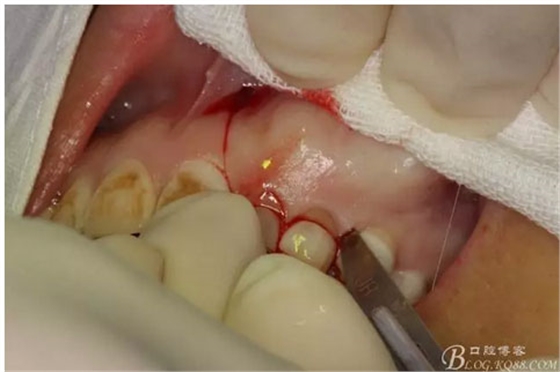

圖7.行左側(cè)乳Ⅱ近中唇側(cè)垂直切口,切透粘骨膜。

圖8. 沿左側(cè)乳Ⅱ、Ⅲ唇側(cè)齦溝內(nèi)切口至24部位。

圖9.從兩個(gè)切口的連接處開(kāi)始翻瓣。全厚瓣。